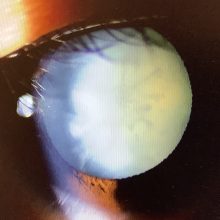

今日、『3月前から左眼が見えにくい』と受診された31歳の男性の方は、左眼の視力が 手動弁まで低下し、原因は白内障でした。白内障もこんなに視力が下がることは多くはないのですが、この男性の場合、白内障が真っ白に濁ってしまう“成熟白内障”という濁りが強いタイプで視力がだいぶ下がってしまいます。

白内障はどんなに濁りが強くなって見えにくくなり、視力が下がっても、白内障の濁りを取り除き、新たなレンズをきれいに入れ、手術さえうまくいけば、術後は見やすくなり手遅れということはありません。しかし、白内障が進行すれば、当然、手術の難易度は上がり“手術がうまくいけば”という前提条件が崩れやすくなってきます。特にこの方のような成熟白内障では水晶体が乳化して真っ白に膨張して濁り、水晶体内の圧が上がってしまうので、水晶体の表面を切開する操作が難しく手術の難易度が上がってしまいます。

この患者さんは成熟白内障でちょっと手術は大変になるかもしれませんが、なんとかうまく見えるようになるように頑張りたいと思います。